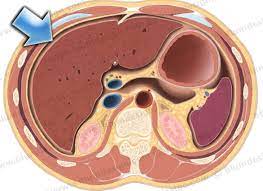

3. Imaging of Peritoneal Anatomy for Radiology Residents By Dr. Zainab Vora Explains

If you’ve always found peritoneal anatomy confusing, you’re not alone. In this honest and relatable session, Dr. Zainab Vora takes you through a step-by-step conceptual radiology approach to understanding the peritoneum, using CT images and real-world analogies.

Key learning points:

• Basic peritoneal anatomy

• Peritoneal ligaments, omentum, and mesentery

• How to trace bowel loops on CT

• The role of imaging modalities (CT, MRI, PET) in peritoneal disease

• Common mistakes and what surgeons actually want from radiologists

Click Here to Watch